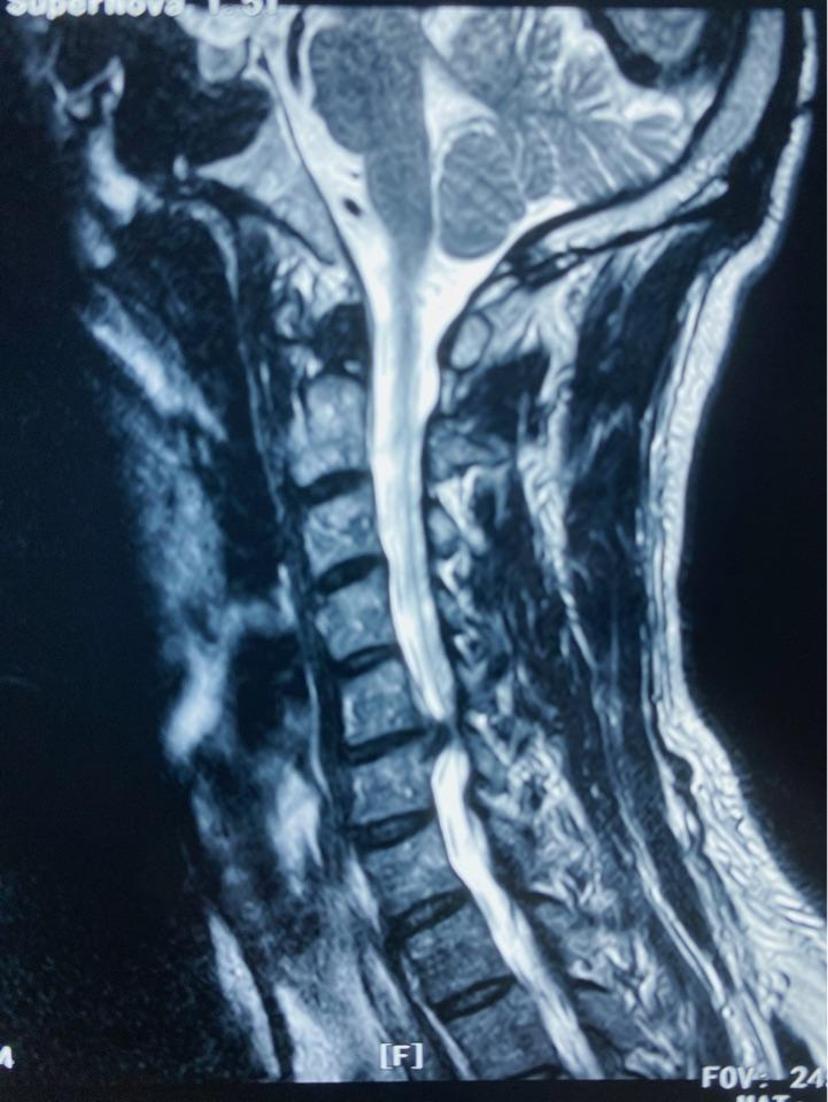

四肢麻木无力,走路不稳,平时需要家人搀扶、拄拐杖走路,行颈前路微创手术,术程不到1小时,切口2cm,术中出血不到10ml,术后第二天下地自行走路,第三天自己弃拐带小跑出院!颈5-6椎间盘突出继发椎管狭窄,脊髓神经严重受压左侧神经严重受压颈椎反弓术中完整取出压迫脊髓神经的椎间盘术后片子位置良好,颈椎反弓完全纠正术后第三天四肢力量明显恢复,麻木感消失,自己甩掉拐杖带小跑出院